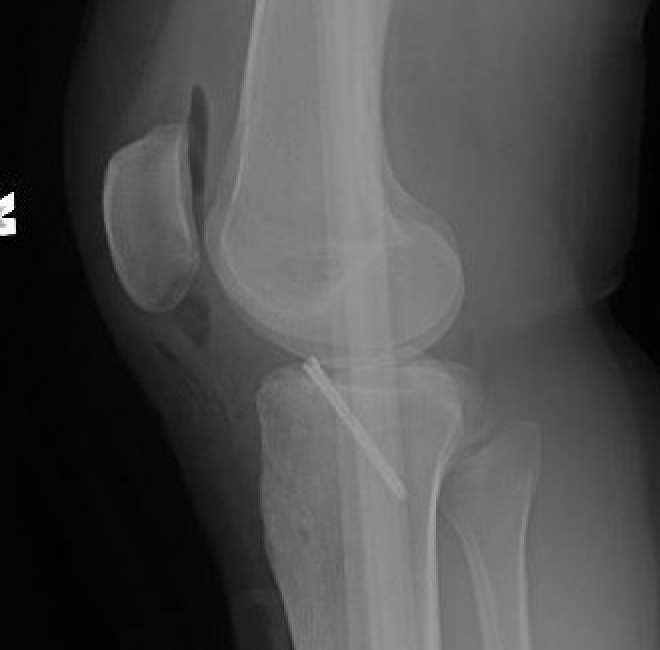

Xray

Xray showing likely Type II with anterior hinging